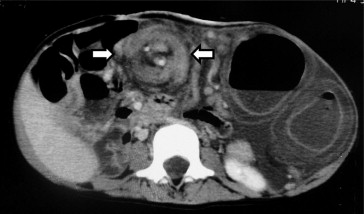

A 5-year-old female was admitted to our institution due to a marked abdominal distention and frequent vomiting. She had previously been diagnosed with prune belly syndrome with multiple congenital anomalies, including atresia ani, during the neonatal period. A transverse loop colostomy and cystotomy had been performed due to the atresia ani during the neonatal period. Mental retardation had also been diagnosed. An abdominal plain X-ray film showed a markedly distended intestine. A Nelaton catheter was inserted from the colostomy into the dilated intestine under fluoroscopic imaging, and a large amount of gas blew out through the tube, resulting in temporary improvement of her symptoms. However, her abdomen gradually became distended again later. A contrast study through the stoma showed a bird’s beak sign-like finding in the site proximal to the colostomy (Fig. 1), and the contrast CT scan revealed the whirl sign at the right upper abdomen near the colostomy (Fig. 2). An emergency laparotomy was performed because the CT scan findings suggested the presence of the volvulus, and the symptoms were recurrent in spite of deflation by means of a catheter. The surgical findings showed a nonrotation type of malrotation and that the total colon therefore was not fixed to the retroperitoneum. A volvulus of the colon existed, with ischemic changes at the site proximal to the colostomy. The dilation of the colon in the site proximal to the colostomy was also noticed. The release of the colonic volvulus led to the improvement of its ischemia. Therefore, a resection of the colon was not performed. The previous loop colostomy was divided into proximal site and distal site. The proximal site of the previous colostomy was fixed to the abdominal wall as a new end colostomy, while the distal site of the previous colostomy was completely closed. The patient’s postoperative course was uneventful, and she was discharged on the 16th day after the operation. During the 2-year follow-up period, no further symptoms of volvulus have been observed.

CT demonstrated the “whirl sign” (arrows), with a twisted mesocolon encircling ...

Figure 2.

CT demonstrated the “whirl sign” (arrows), with a twisted mesocolon encircling the mesocolic vascular pedicle serving the affected segment of the colon.